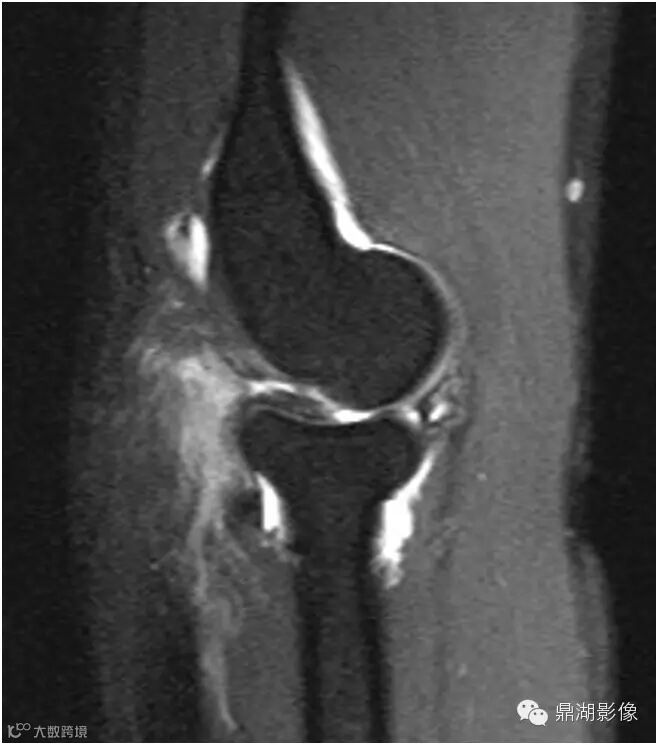

抑脂序列冠状位及矢状位T2WI显示在后外侧肱桡关节间隙内增厚的滑膜皱襞隆起并折叠(箭头)。

皱襞内可见高信号影,测量超过3毫米的厚度,并覆盖了几乎一半的桡骨头关节面。并可见易被误认为是肱骨小头缺损的正常肱骨头(*)。